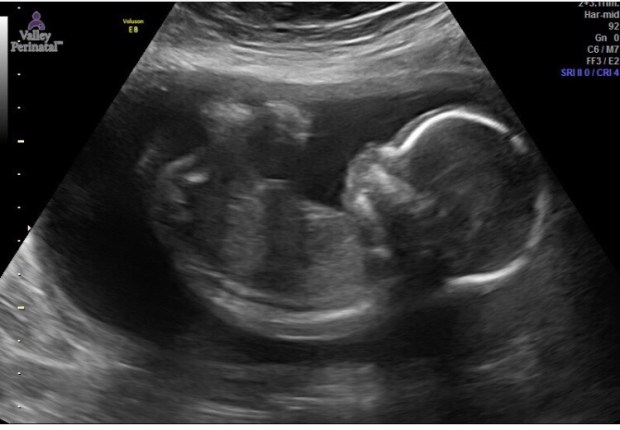

At the ultrasound, we first checked on our baby’s health and were relieved when told everything was looking healthy. We heard our baby’s fast heartbeat and saw her move around playfully. It was actually pretty cute; she would move her hands around and even looked up at us for a second, long enough for us to “oooh” and “aaaa” about it.

The last thing we looked at was our baby’s gender. It was pretty obvious to hubs and I that it was a girl from the very beginning of the ultrasound. We glanced at each other and whispered “girl” but we still hadn’t officially heard the words so we had to wait anxiously. Finally, when we were told it was a girl, I completely and unexpectedly balled my eyes out. The sonologist kept asking “Do you see it, do you see what I am looking at” and I just couldn’t speak…only cry! I had the happy ugly cry look all over my face and I just couldn’t help it! I glanced over at hubs and he looked so confused…HA…sorry hubs, emotional preggo over here!